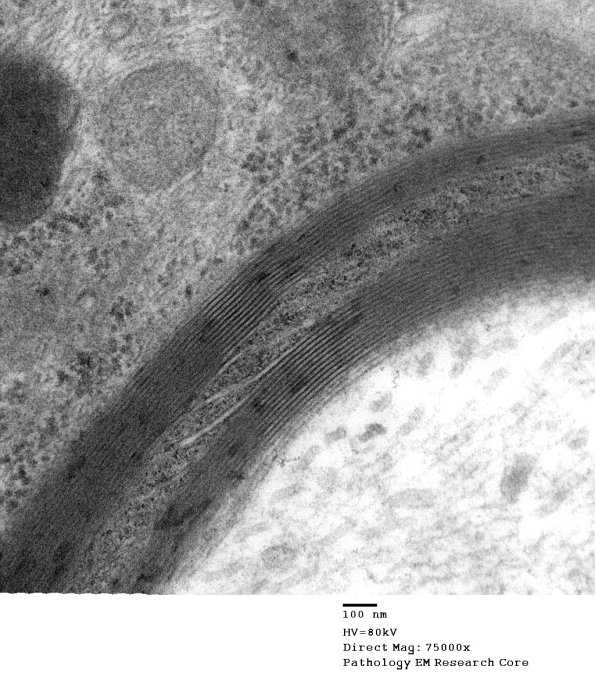

Higher magnification of image #6A3. (electron micrograph)